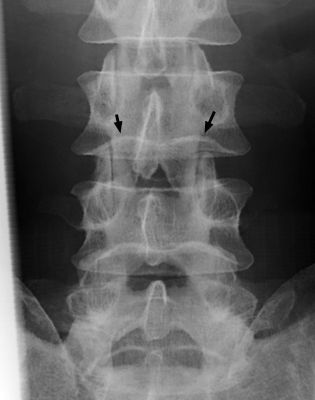

Diagnosis:Normal spine Discussion:Frontal and lateral radiograph of the lumbar spine with curvature of the inferior endplate of the 4th and 5th lumbar vertebrae, which mimics the curvature of Cupid's bow aimed cephalad. The unusual, non-flat surface of the inferior endplate is a normal variant, and need not be misinterpreted as inherent osseous abnormality or adjacent pathological process. References: